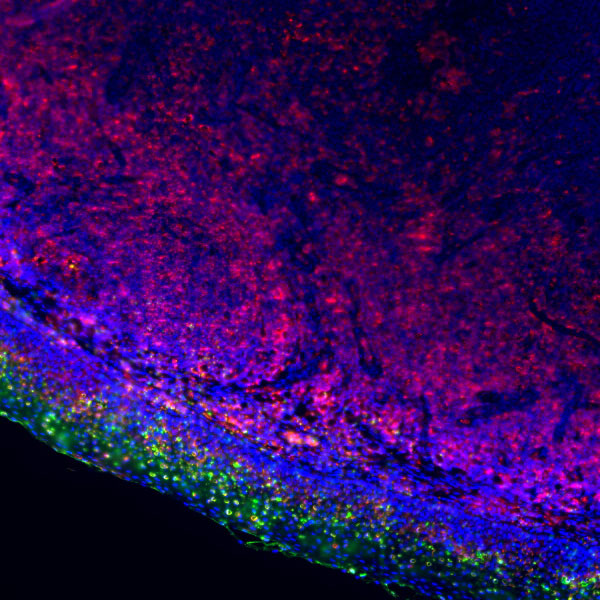

Explore Our Recommended Popular Products

30,000+ high- quality products available online

Primary Antibodies, Secondary Antibodies, mIHC Kits, ELISA Kits, Proteins, Molecular Biology Products,Cell Lines,Reagents ...